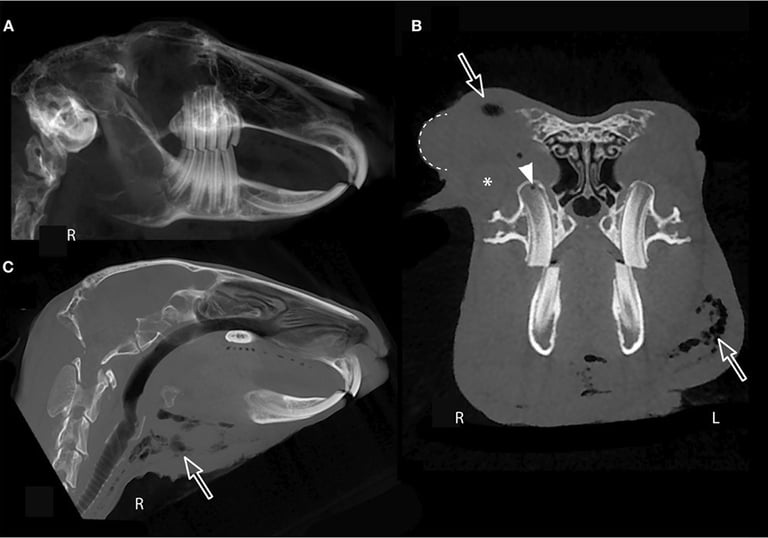

Żeby ocenić struktury, których nie widać z zewnątrz ani od strony jamy ustnej (np. budowę "korzeni" zębów i kości czaszki, strukturę nosa i zatok czy wnętrze puszek bębenkowych) konieczne jest wykonanie badania obrazowego: zdjęć RTG lub tomografii komputerowej.

pozwala bardzo dokładnie (w 3D) ocenić struktury czaszki, w tym wnętrze nosa i zatok oraz puszki bębenkowe

umożliwia zobrazowanie nawet tak małych i głęboko położonych struktur jak kostna część ucha wewnętrznego

bardzo szczegółowy, ale płaski, dwuwymiarowy (2D) obraz

struktury czaszki mogą się na siebie nakładać, utrudniając ocenę detali

proste badanie, świetne do zobrazowania większości zębów, ale nie pozwala na ocenę wnętrza nosa i puszek bębenkowych

"Clinical Application of Cone Beam Computed Tomography of the Rabbit Head: Part 2 — Dental Disease"